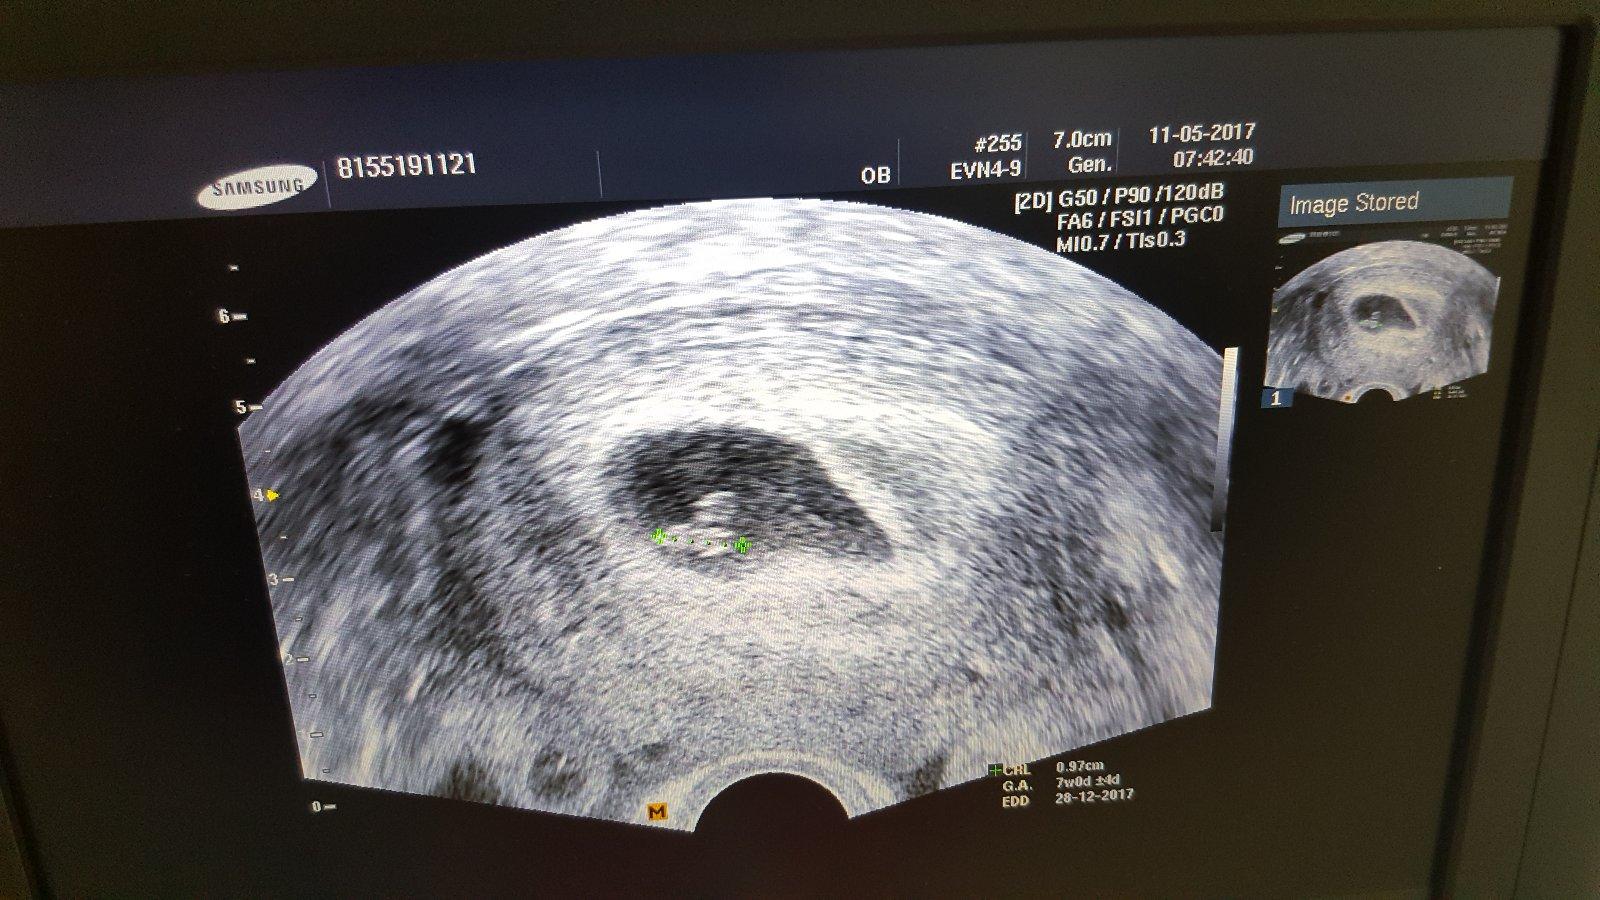

Ahoj holky. Jak jste na tom? Nase ❤ meri 0,97cm a jsme 7+0..